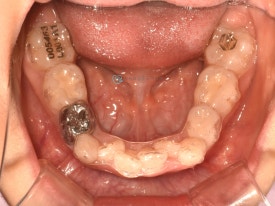

투명교정 10개월차입니다.

치료 후 - 유치 어금니들이 빠지고 영구치가 맹출하고 있습니다.송곳니가 나올 공간을 충분히 마련하며 확장하여 고른치열을 완성했습니다.

자세히 보면 아래 영구치 어금니의 충치도 치료하는 과정에서 깨끗하게 레진치료 해주었습니다. 교정하면서 충치검진이나 치료를 위해 다른 치과에 내원하지 않아도 된다는 점이 바쁜 우리 아이들에게는 큰 장점으로 다가오는 것 같습니다. 서울효앤주니어치과에서 교정체크 = 충치검진

치료 전 - 위아래 심한 공간 부족이 관찰됩니다.자세히 보면 아래 영구치 어금니의 충치도 치료하는 과정에서 깨끗하게 레진치료 해주었습니다. 교정하면서 충치검진이나 치료를 위해 다른 치과에 내원하지 않아도 된다는 점이 바쁜 우리 아이들에게는 큰 장점으로 다가오는 것 같습니다. 서울효앤주니어치과에서 교정체크 = 충치검진